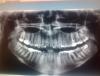

IvanK Опубликовано 10 ноября, 2012 Поделиться Опубликовано 10 ноября, 2012 На здоровье.А есть возможность сделать снимок ОПТГ (ортопантомограмму), может еще что "интересное" найдем Ссылка на комментарий

таня в Опубликовано 11 ноября, 2012 Автор Поделиться Опубликовано 11 ноября, 2012 Ссылка на комментарий

таня в Опубликовано 11 ноября, 2012 Автор Поделиться Опубликовано 11 ноября, 2012 (изменено) снимок сделан в середине октября.после удалили 6 верх.справаДелали мне его в районе,у нас такого аппарата в больнице нет.Наверно стоит сделать повторный снимок.что скажете?? Изменено 11 ноября, 2012 пользователем таня в Ссылка на комментарий

IvanK Опубликовано 11 ноября, 2012 Поделиться Опубликовано 11 ноября, 2012 Нужно обязательно пользоваться зубной нитью.Остальные 6-ки нужно перелечить Ссылка на комментарий